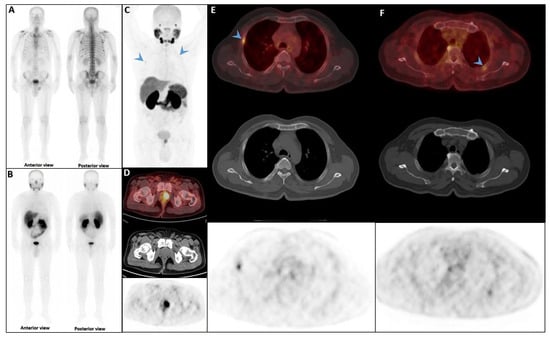

Pleuro-Pulmonary Extramedullary Plasmacytomas in Multiple Myeloma: A 15-Year Experience from a Tertiary Center

Background/Objectives: Extramedullary involvement in multiple myeloma represents an aggressive disease phenotype, associated with reduced survival and an unfavorable prognosis. Thoracic manifestations are rare and remain poorly characterized in the literature. Methods: We conducted a retrospective, single-center study at the Fundeni Clinical Institute, including patients diagnosed with multiple myeloma between February 2010 and February 2025. The study cohort consisted of 34 patients with infiltration of the pulmonary parenchyma, pleura, or the presence of myelomatous pleural effusion. Diagnosis was confirmed using a combination of imaging modalities (computed tomography or magnetic resonance imaging), cytological examination, immunophenotyping, and histopathological confirmation whenever feasible. Results: Out of a total of 2012 patients with multiple myeloma, the incidence of pleuro-pulmonary extramedullary involvement was 1.6%. The median age at diagnosis was 58 years. Pleuro-pulmonary disease was present at initial diagnosis in 26.5% of cases, while 73.5% developed it at relapse. The most common presentation involved combined pleural involvement and myelomatous effusion (70.6%). Adverse prognostic markers included elevated β2-microglobulin levels (in over 80% of cases) and increased lactate dehydrogenase (LDH) in approximately 50%. Cytogenetic abnormalities such as del(17p), t(4;14), t(14;16), t(11;14), and 1q gain were identified. The median overall survival (OS) from the diagnosis of pleuro-pulmonary extramedullary disease was 16 months, with a 2-year survival rate of 25%. No patient survived beyond 5 years. The median progression-free survival (PFS) was 9 months. Conclusions: Our findings confirm the aggressive clinical course and poor prognosis of these disease manifestations, mainly when they occur at relapse. In the absence of standardized treatment guidelines, individualizing therapy and accessing novel strategies may be essential for improving patient survival.